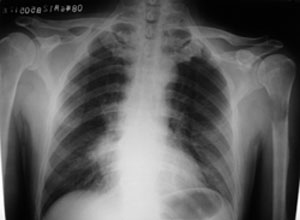

性别 男  62岁 因咳嗽及左肱骨剧烈痛疼数天来院检查。

右中央型肺癌并肱骨转移。

考虑右肺中叶肺癌并左肱骨转移伴病理性骨折。

支持右肺中心型肺癌并肺内及左肱骨转移伴病理性骨折

右肺中心型肺癌并中叶不张,左肱骨溶骨性转移并病理骨折。